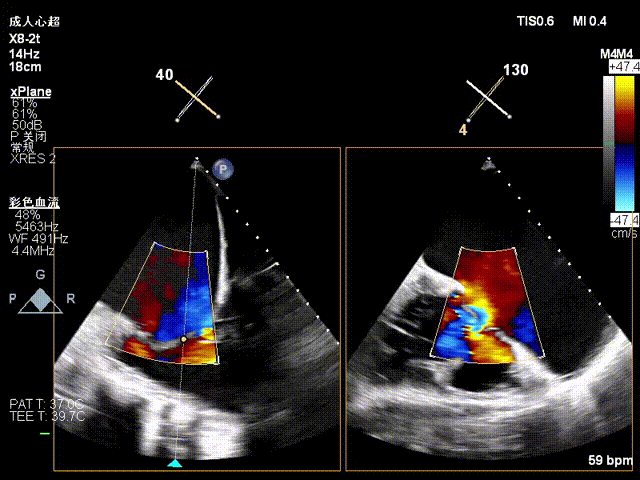

1.TR Reduction: Overall reduction greater than 3+ (decreased from massive 6+ to moderate-to-severe 3+).

Massive 6+

Moderate-to-Severe 3+